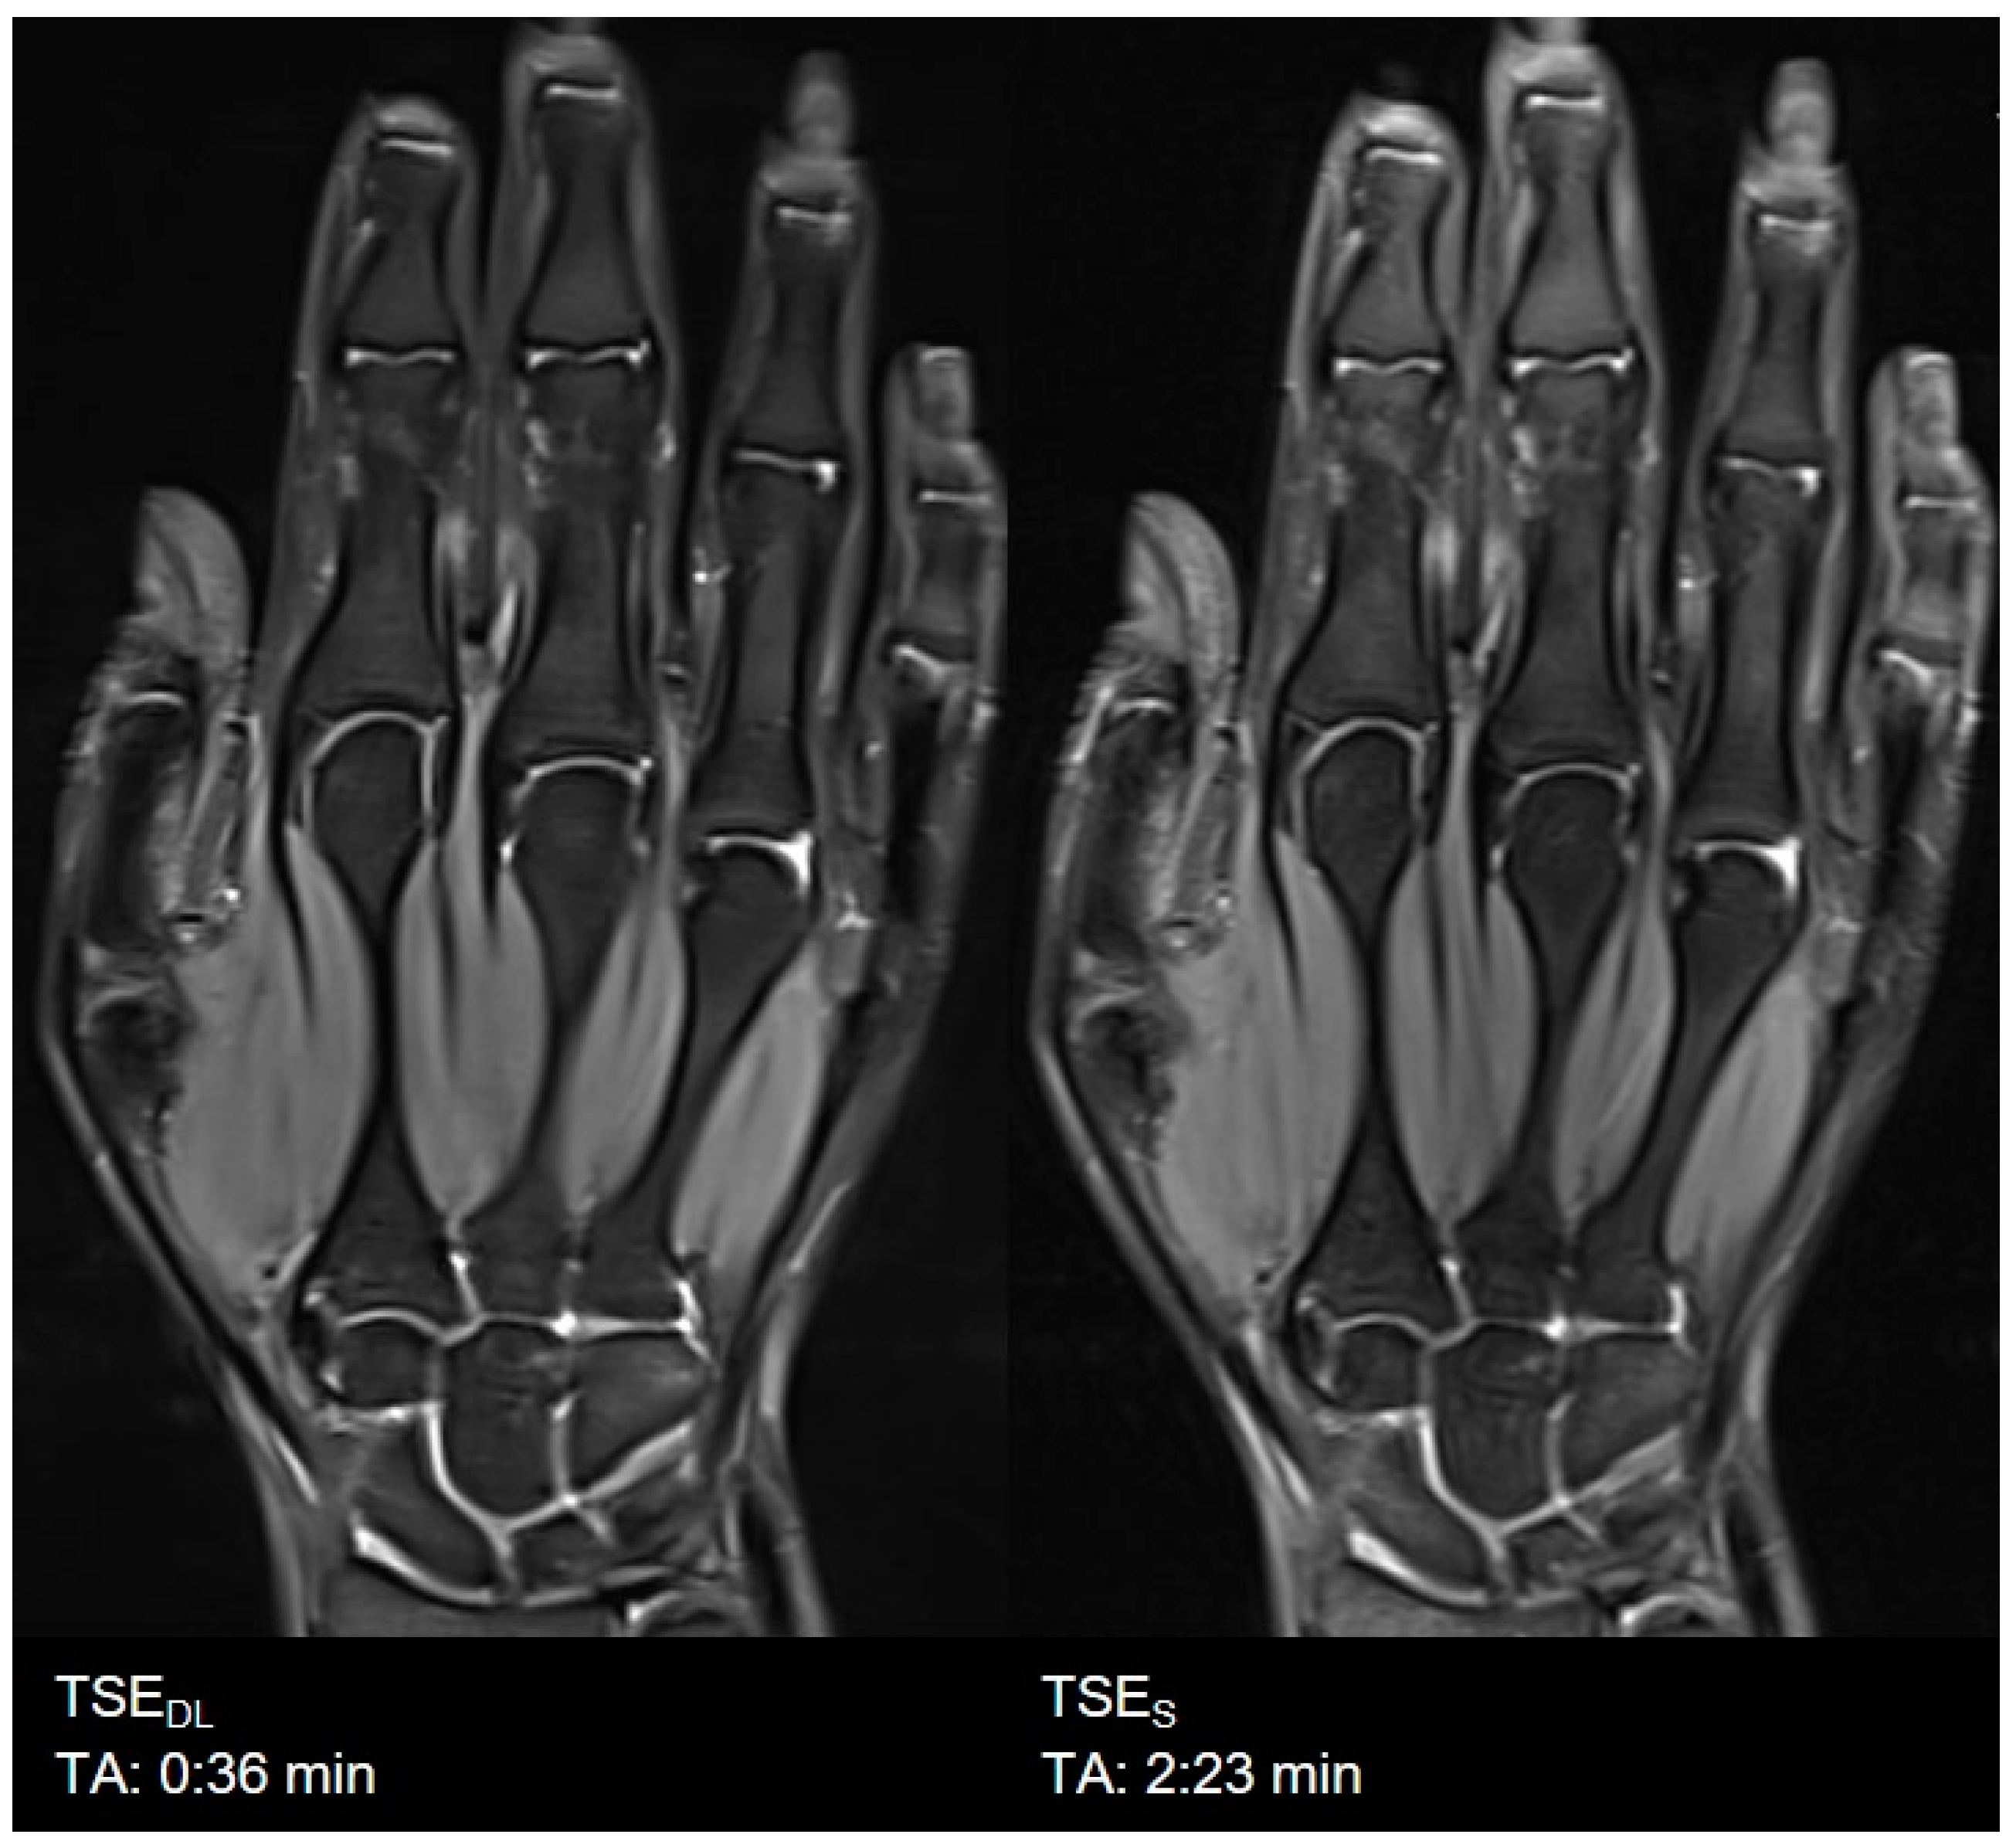

| Hand | TSES | TSE PD FS | coronal | 2:23 | 200 | 0.5 × 0.5 × 2.0 | 2 | 1 | 0 | 3000 | 41 | 150 | 121 | 13.6 |

| axial | 4:40 | 180 | 0.5 × 0.5 × 2.0 | 2 | 2 | 0 | 3310 | 42 | 150 | 121 | 13.9 | |||

| TSEDL | TSE PD FS | coronal | 0:36 | 200 | 0.5 × 0.5 × 2.0 | 1 | 1 | 3 | 3000 | 44 | 150 | 119 | 14.7 | |

| axial | 1:23 | 180 | 0.5 × 0.5 × 2.0 | 1 | 2 | 2 | 3190 | 42 | 150 | 119 | 14.1 |